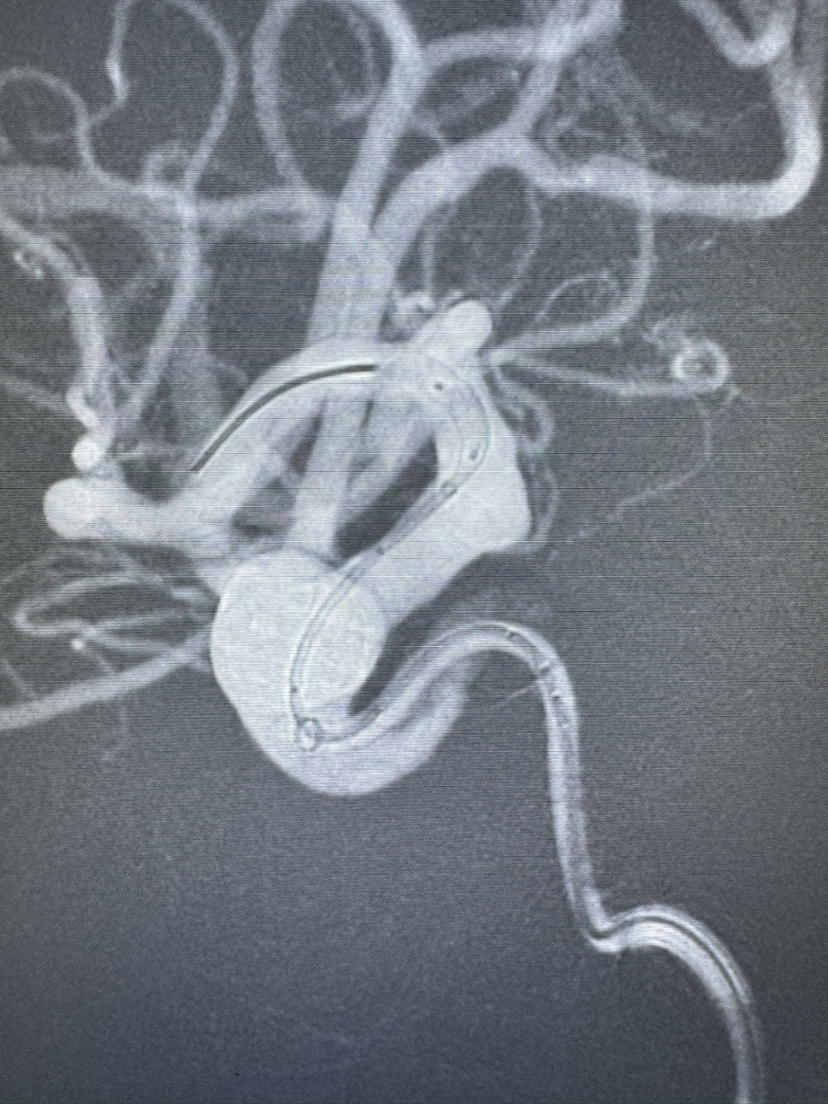

Lattice 支架治疗眼动脉动脉瘤,Scepter c 球囊后扩辅助海绵窦段支架打开